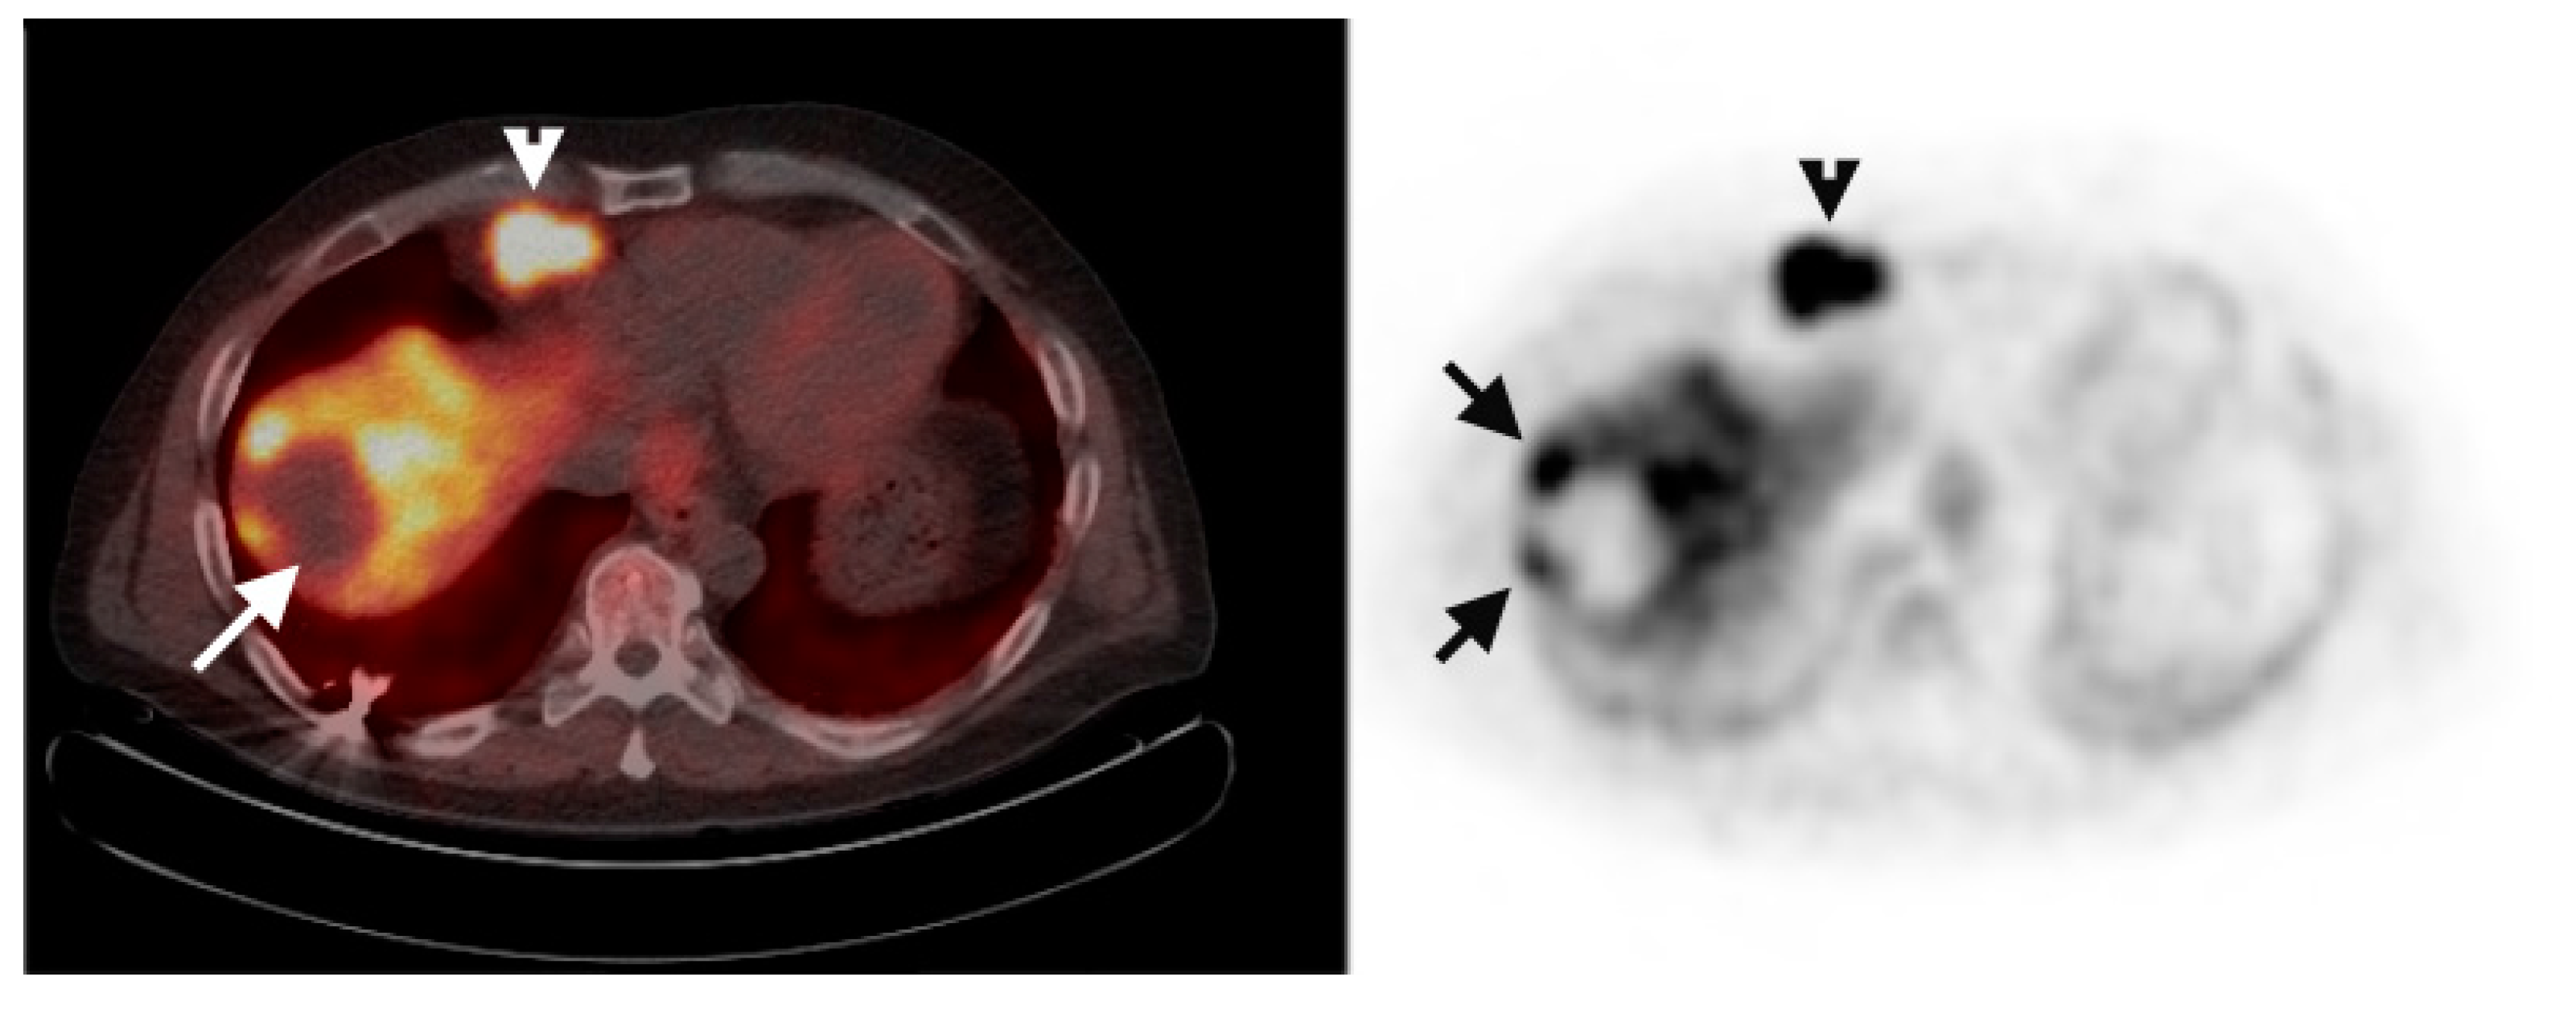

Multiple foci of increased FCh uptake in the liver consistent with multifocal or multinodular HCC (example, Figure 1) were noted in 8 of the 13 patients with increased primary tumor uptake. Of these, the areas of increased FCh uptake were adjacent to the treatment site (examples, Figure 2 and Figure 3) in 2 patients treated by local tumor ablation and 1 patient treated by liver resection. In one newly diagnosed case, PET demonstrated heterogeneous tumor FCh uptake with increased peripheral uptake and markedly diminished central uptake (Figure 4). Pathology in this case revealed a highly-necrotic tumor with Edmondson-Steiner grade 3 differentiation.

Figure 2.

Recurrent HCC surrounding previous radiofrequency ablation site. PET/CT (left) shows absent FCh uptake (white arrow) in an area of the liver where HCC was previously treated by radiofrequency ablation. Corresponding PET (right) clearly shows multiple foci of increased FCh uptake surrounding the ablation site consistent with recurrent HCC (arrows). A pulmonary metastasis was also detected in this patient (arrowheads).